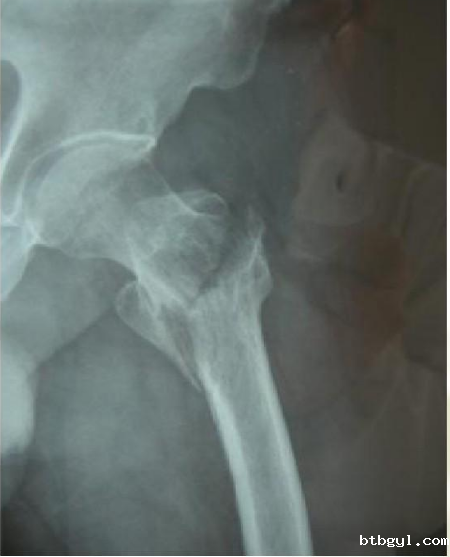

前段时间,百岁高龄的赵奶奶在家下楼时不慎踩滑摔倒受伤,因“左侧股骨转子间骨折”收入骨科(创伤中心)住院治疗。入院后赵奶奶及家人非常希望通过治疗后能站起来,下床自由行走。由于患者超高龄,基础性疾病多(合并高血压、肺部感染、双侧胸腔积液、肺气肿、硬膜下积液、贫血等多种疾病),心脑肺储备功能差,手术及麻醉风险极大。骨科(创伤中心)负责人韩雪峰、管床医生周成彬联合麻醉科手术室医护团队多次对老人的病情进行充分的术前评估,制定周密麻醉手术方案,拟采用技术成熟的椎管内麻醉下行股骨转子间骨折闭合复位髓腔钉内固定术。入院第三天,两个团队精细配合,顺利完成手术。整个手术过程老人呼吸平稳、循环稳定,尤其是麻醉科主治医师范瀚文全程陪伴赵奶奶,对术中容量管控、疼痛管理进行精细化处置。术后第二天,赵奶奶已能在助行器辅助下地行走。